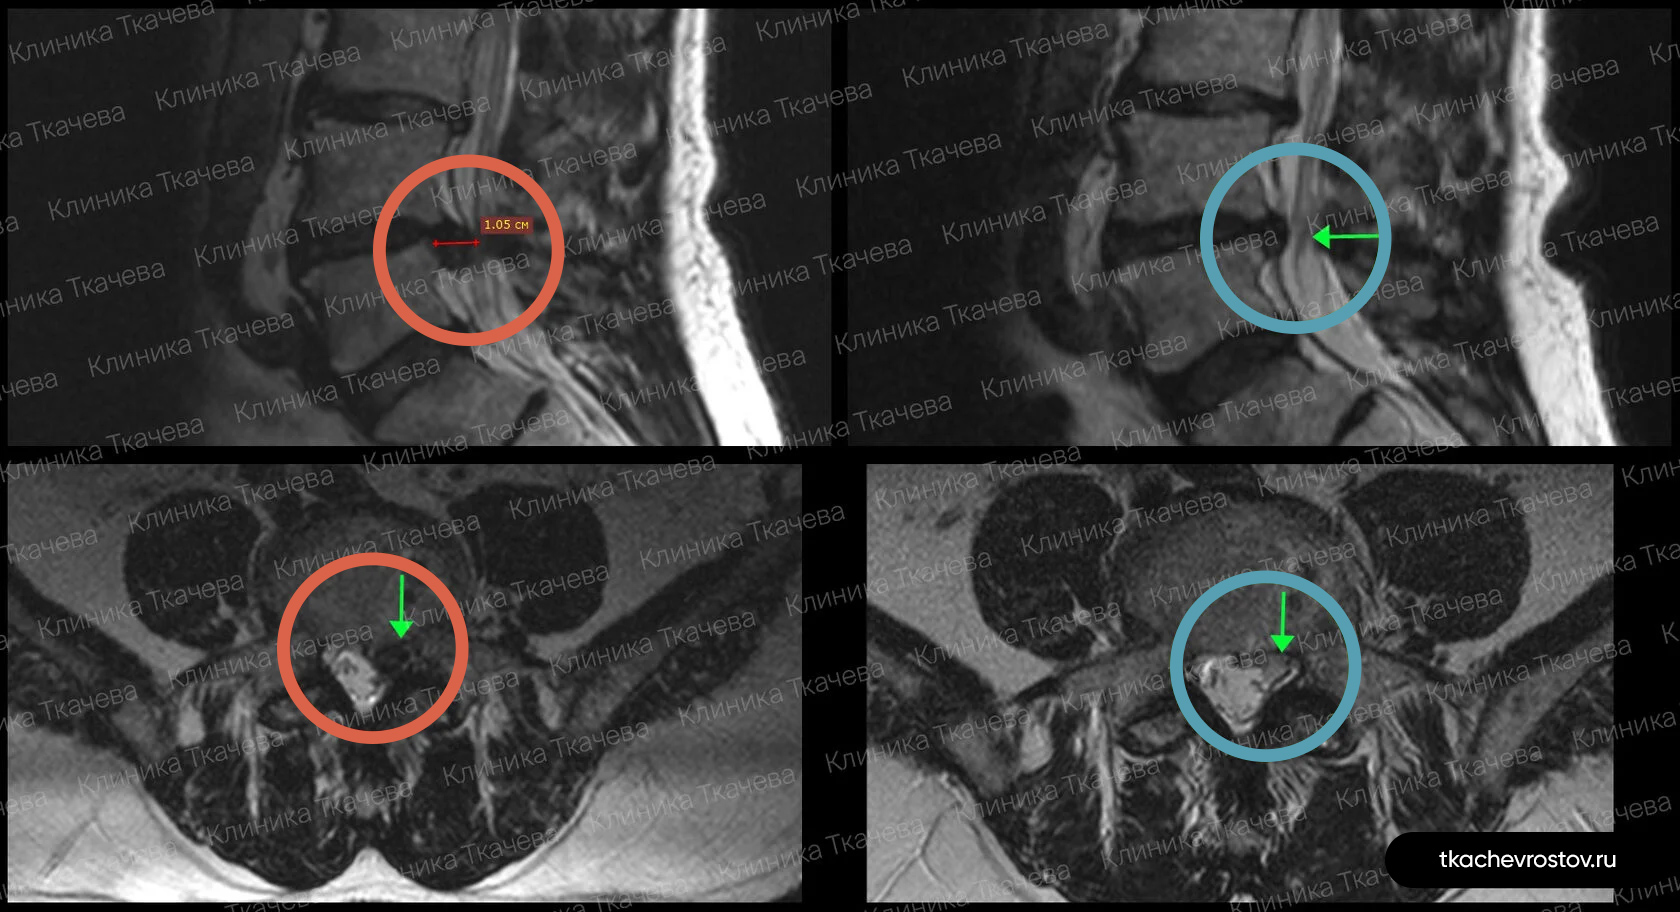

Лечение грыжи в шейном отделе C6-C7

Женщина. Грыжа в шейном отделе C6-C7 1.8х0.8см. Из-за боли передвигалась по стеночке. Отказалась от операции по квоте – замена диска на имплант.

ДО:

- Больно дышать и говорить

- Какие-либо движения головы приносили жуткую боль

- Правая рука не слушалась, частично онемели ладонь и пальцы руки

- Обезболивающие, блокады, капельницы. Ничего не помогло

- Потеря трудоспособности и ограничение жизнедеятельности

ПОСЛЕ 1 курса:

✓ Наступила резорбция грыжи

✓ Наступило улучшения общего состояния

✓ Стала лучше работать правая рука

✓ Ушло частичное онемение

✓ Голова стала поворачиваться во все стороны

✓ Ушла выраженная боль и напряжение в шее

✓ Пациентка смогла сесть за руль

ПОСЛЕ 2 курса:

✓ Полная резорбция грыжи

✓ Восстановление всех двигательных функций

✓ Прекрасное самочувствие

Всё лечение заняло полгода (2 курса по 15 дней).